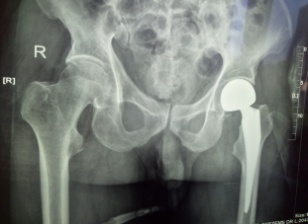

患者王XX,男80歲,前列腺癌骨轉(zhuǎn)移導(dǎo)致病理性骨折,合并房顫、高血壓、冠心病。